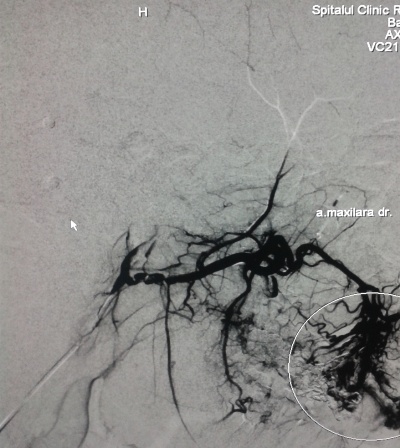

În secţia Chirurgie endovasculară s-a adresat pacientul S., bărbat de 30 ani, cu o formaţiune tumorală a feţei, cu senzaţie de pulsaţie permanentă, cu dureri periodice şi sîngerări frecvente la periaj dentar. Formaţiunea s-a dezvoltat treptat, iar în perioada pubertară a înregistrat o creştere accelerată. O serie de investigaţii (Angio-RMN şi Duplexul arterial) a stabilit diagnosticul de Malformaţie arteriovenoasă, care este o anomalie vasculară activă hemodinamic, cu flux sanguin rapid, cu afluenţi arteriali şi vene dilatate.

S-a utilizat procedura minim-invazivă endovasculară, care constă în cateterizarea supraselectivă a aferentelor arteriale a malformaţiei, cu embolizarea ulterioară a acestora pîna la stoparea fluxului de sînge prin malformaţie. De obicei, o astfel de procedură durează de la 40 minute pînă la două ore. Extrem de rar pot apărea complicaţii de ordin local (hematom, tromboză, fistulă) sau la nivelul regiunii malformaţiei (ulceraţie a mucoasei cu hemoragie, embolizarea ţesutului nedorit cu necroze). Scopul intervenţiei a fost de a micşora volumul malformaţiei (cu lichidarea ei în varianta ideală), dar şi de a atribui un aspect estetic. Astfel de proceduri pot fi asociate cu metode chirurgicale reconstructive de excizie a malformaţiei sau sclerozare, în cazuri selecte, care pot produce deformaţiuni şi cicatrici nedorite.